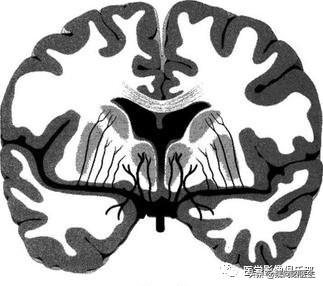

腔隙性脑梗死:是脑穿支小动脉闭塞引起的深部脑组织较小面积的缺血性坏死,主要病因是高血压和脑动脉硬化,好发部位为基底核区和丘脑区,也可发生于脑干、小脑等区域,可多发。

由于这些穿支小动脉的供血区域通常没有侧支循环,所以很容易发生缺血性梗死,形成直径0.2~15mm的囊性病灶,坏死组织被吸收后,残留下来小囊腔,即称为“腔隙性脑梗死”。